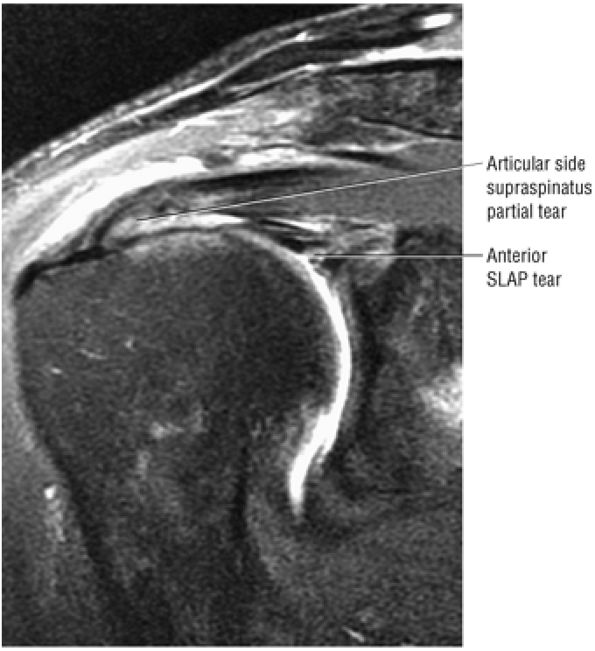

The SLAC lesion is combined with the anterior component of a SLAP 2 tear.

-

The SLAC lesion is a type of instability and not an impingement lesion.

![]() |

|

FIGURE 8.178 ● Potential sites of involvement in microinstability, including the anterior supraspinatus and anterior component of a SLAP 2 in the SLAC lesion; the posterior cuff and posterior component of a SLAP 2 in the posterior peel-back lesion; the classic anterior-to-posterior SLAP 2 lesion; anterosuperior impingement (ASI) involving the superior subscapularis, CHL–SGHL complex, the anterior supraspinatus and anterosuperior labrum, and the middle glenohumeral ligament (MGL) in anterior laxity.